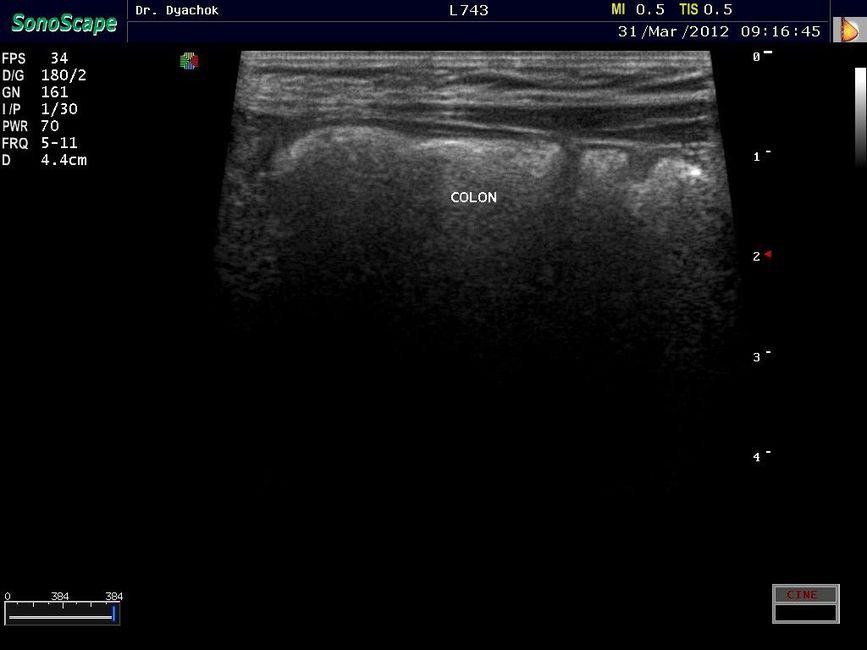

Sonoscape S9 представляет собой топовую переносную ультразвуковую систему, сочетающую инновационный дизайн, современные технологии визуализации и широкие диагностические возможности. Компактный аппарат экспертного класса подтверждает лидирующие позиции компании на рынке портативных ультразвуковых систем.

• Исследования поверхностных и абдоминальных органов